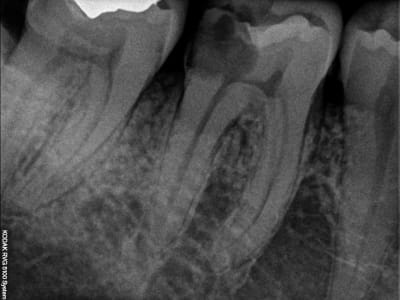

Ben voilà:

For English speaking folks:

E a versão Português, Acabado o Cerec !:

encore une:

Voco va faire des affaires !